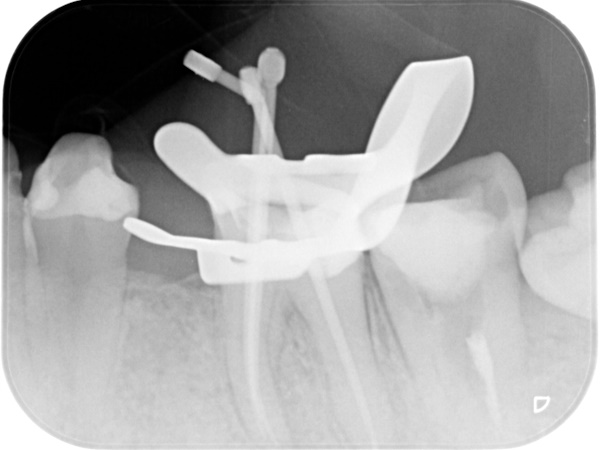

根管治療中(試適時)